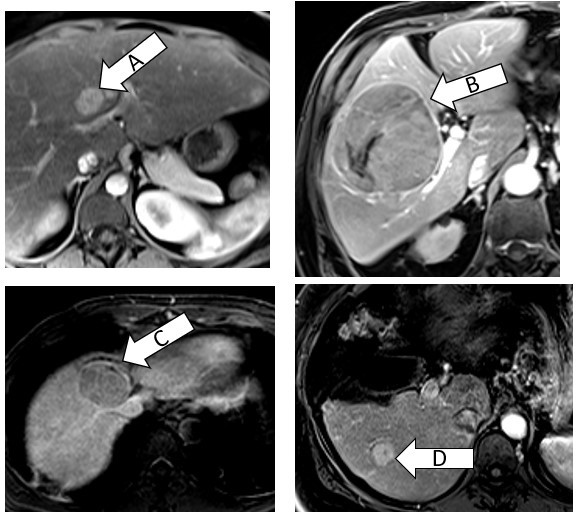

Based only on imaging, which of these is the best ablation candidate?

D

A isn’t great because it’s right up against the central structures with a fair chance of central biliary damage and long-term stricturing. B is too big. C is tucked against the cava-therefore due to heat sink issues, it would be hard or impossible to get all of the tumor. D is under 3cm, away from central structures. Surface/capsular tumors are doable but carry a higher risk of bleeding/seeding; the technical approach also has to be considered as to not burn body wall.